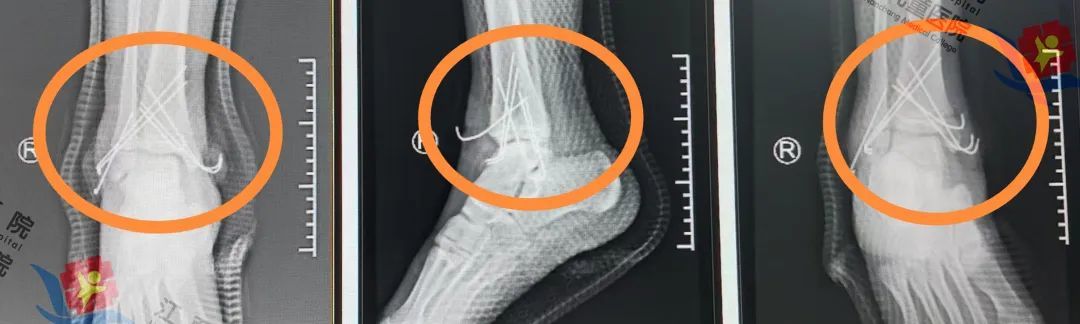

熊志刚、邹俊、杨小刚、李健手术团队与麻醉科手术室密切配合在不切开骨折部位与C型臂透视的情况下采用手法复位将移位的骨折精准复位复位后骨折对位对线良好关节面平整并使用克氏针经皮将骨折固定像“临时内部支架”稳定骨折端同时保留了骨骼生长空间,手术进展顺利。

术后图

目前,航航已出院